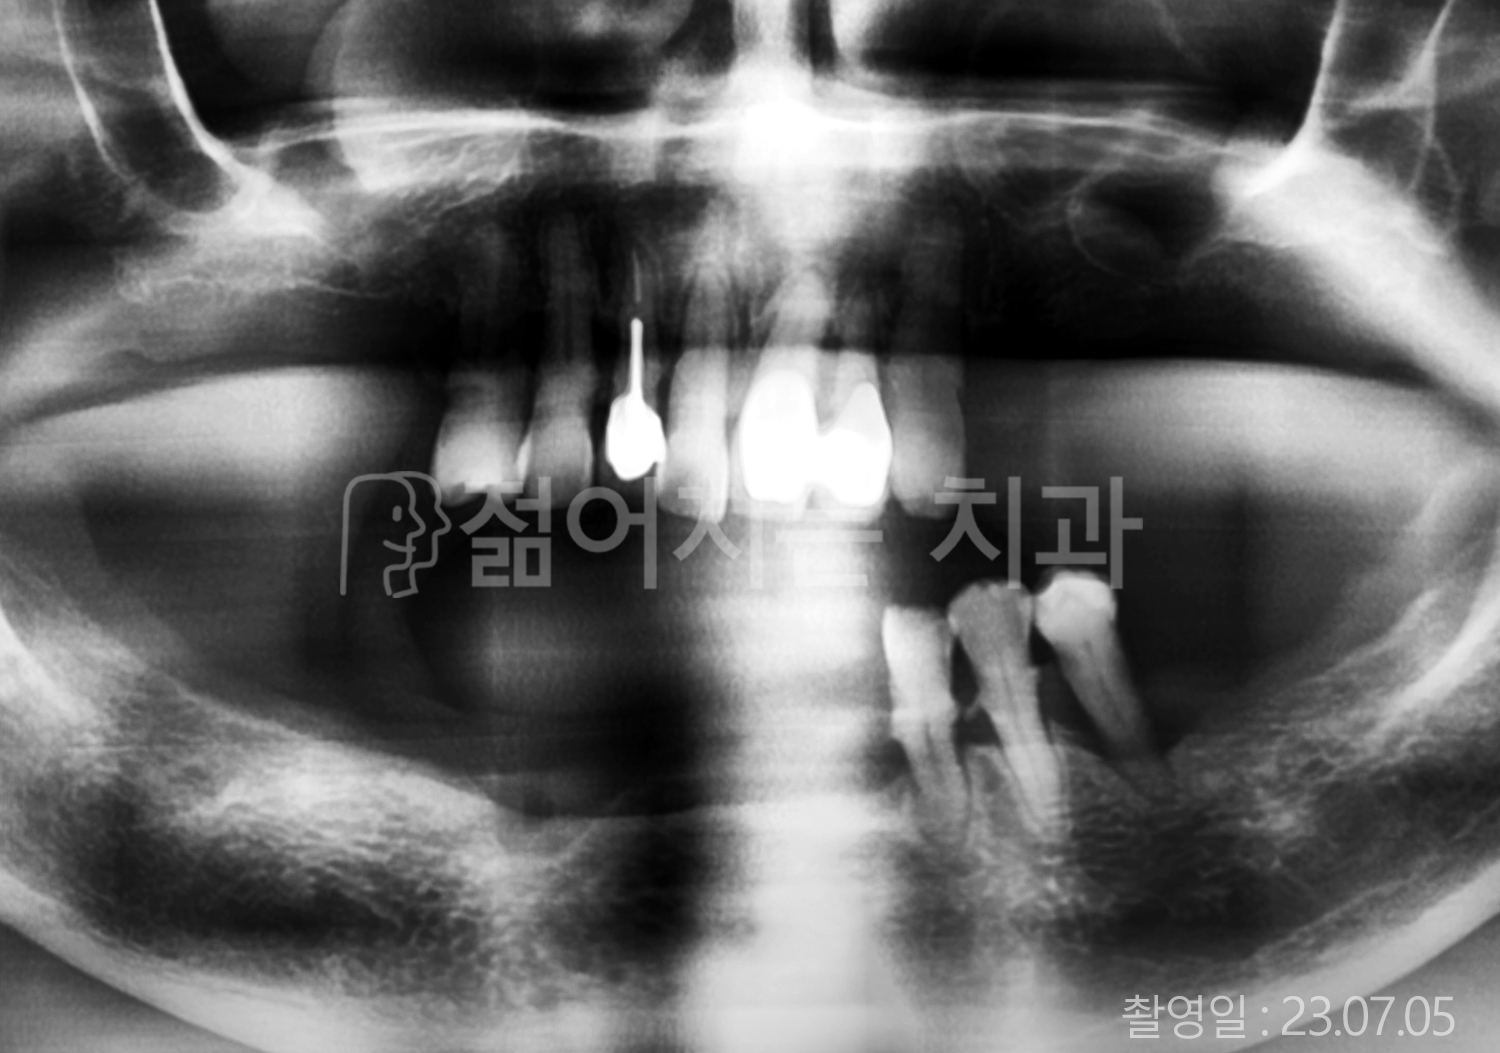

• 60대 고혈압, 고지혈증 전체치아 10개 이상 임플란트

• 70대 전체치아 10개 이상 임플란트

• 60대 전체치아 10개 이상 임플란트

• 50대 전체치아 10개 이상 임플란트

• 50대 고혈압, 고지혈증 전체치아 10개 이상 임플란트

• 60대 고혈압, 당뇨, 고지혈증 전체치아 10개 이상 임플란트

• 80대 고혈압, 당뇨, 골다공증 전체치아 10개 이상 임플란트

• 60대 고혈압 전체치아 10개 이상 임플란트

• 60대 고지혈증 전체치아 10개 이상 임플란트

• 60대 당뇨 전체치아 10개 이상 임플란트